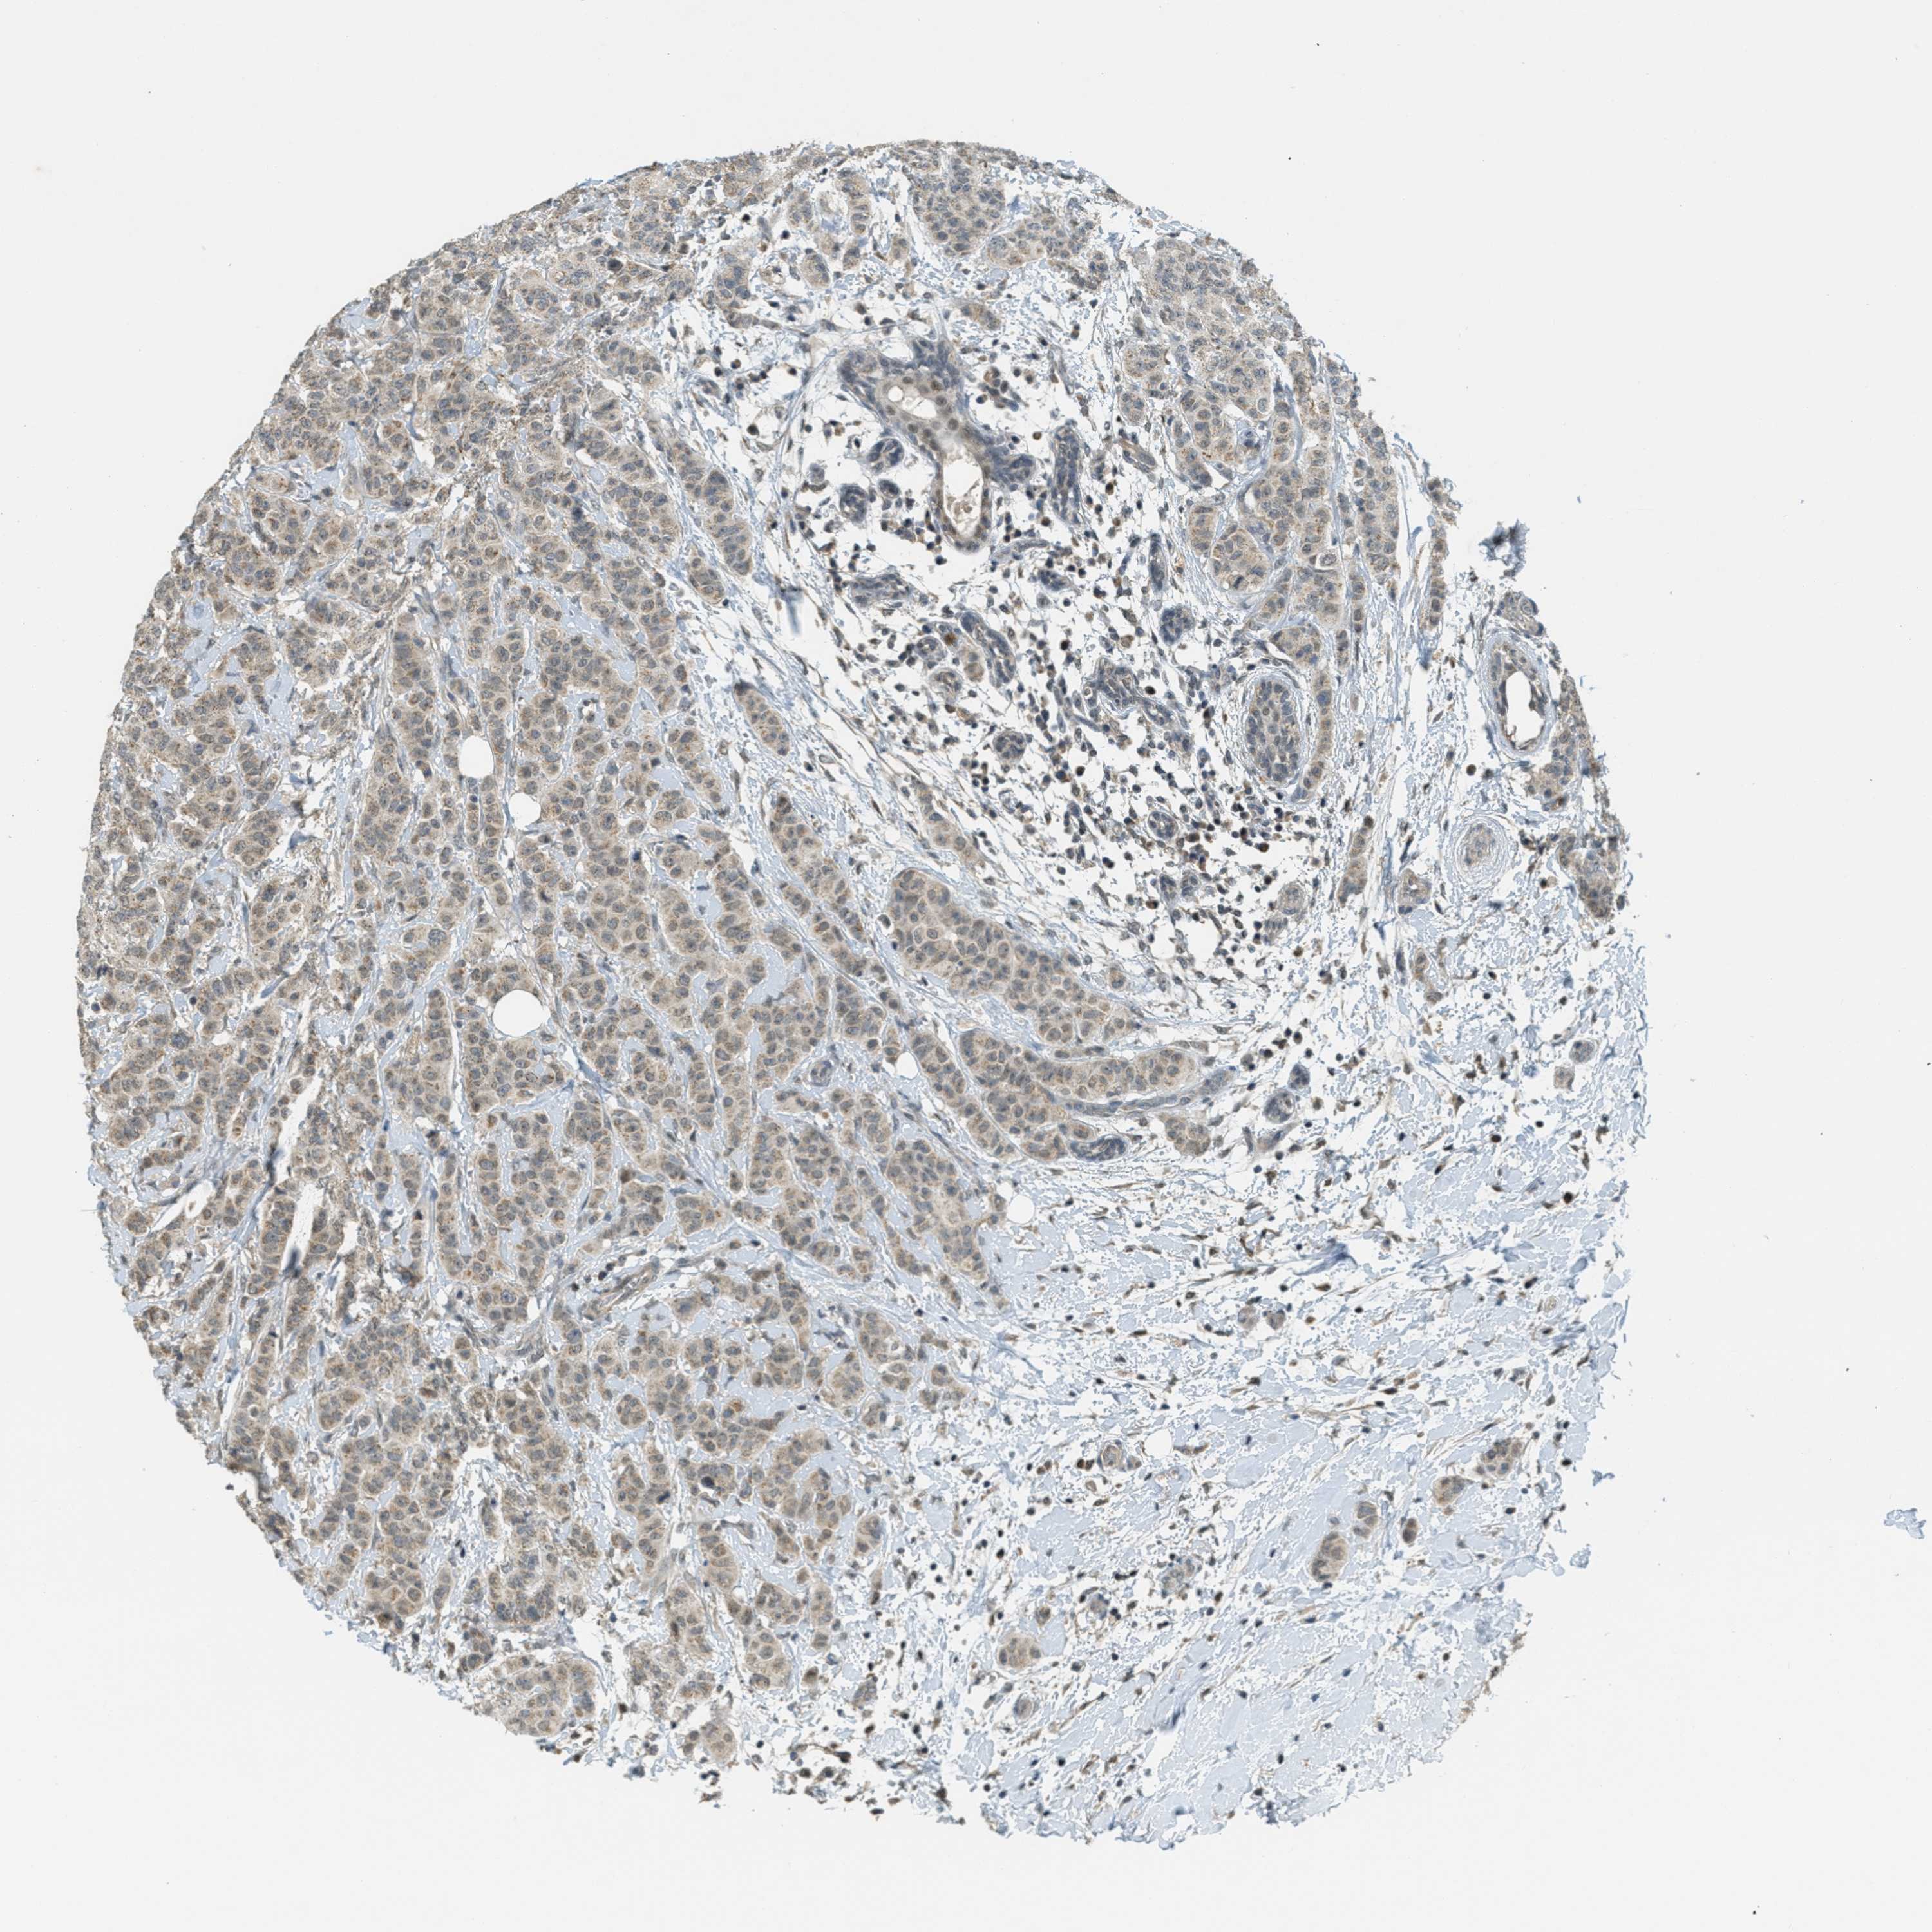

CANCER BREAST CANCER Show tissue menu

BRCA TCGA BRCA VALIDATION PROTEIN EXPRESSION